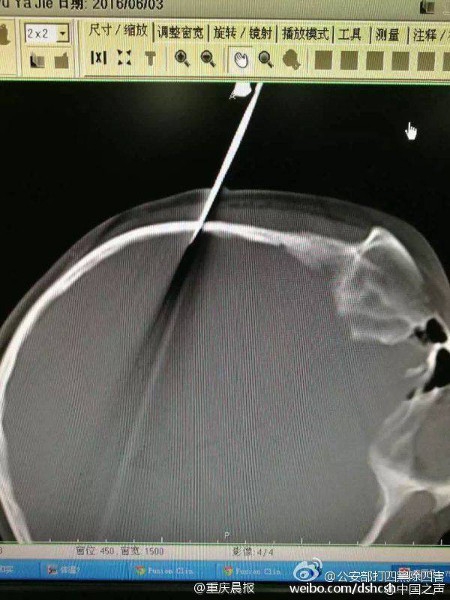

Mới đây, một vụ tai nạn nghiêm trọng đã xảy ra tại Thượng Hải, Trung Quốc khi một ông bố trong lúc nóng giận đã cầm kéo phi vào đầu con gái 10 tuổi của mình. Chiếc kéo đã cắm xuyên qua đầu cô bé đến tận vùng não.

| Bé gái bị cha phi kéo cắm xuyên vào tận não. |

Ngay sau vụ việc, cô bé đã được đưa ngay tới bệnh viện để cấp cứu. Các bác sĩ tiến hành phẫu thuật để rút chiếc kéo dài 15cm ra khỏi phần xương sọ của cô bé. Hiện tại, tình hình sức khỏe của bé gái đã khá hơn, mặc dù cô không thể nhớ chuyện gì đã xảy ra.

| Ảnh chụp cắt lớp não và chiếc kéo. |